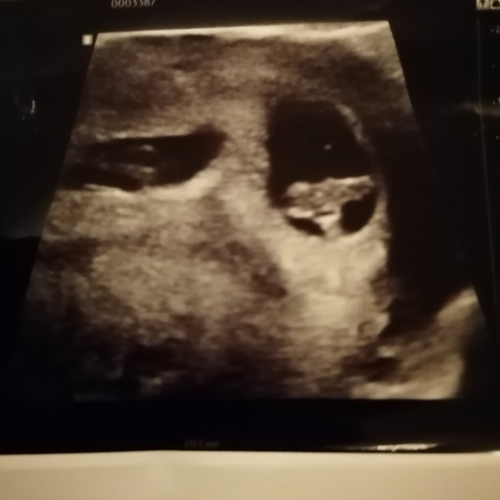

Helaas moeilijk tezien gisteren echo gehad ban 8+5 maar mijn baarmoeder ligt nog wat verder naar achter dus niet zn hele helderen echo maar hartje klopt en alles was goed 😍😍

Ligt een beetje aan de verloskundige waar je zit. Bij de verloskundige waar ik bij zit is dit een medische echo. De vitaliteits echo. Waar ze kijken of er een gezonde zwangerschap is en of het een een of een meerling is. Dit doen ze vaak tussen de 7 en 9 weken.